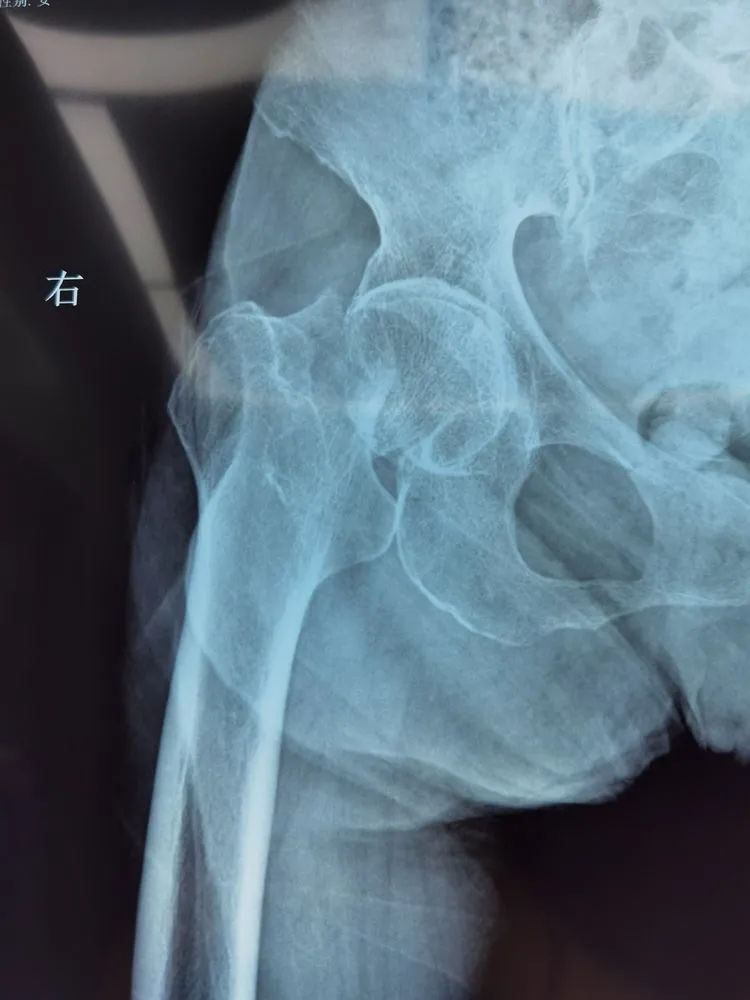

不日前,老人不慎摔伤,剧痛难忍,孝顺的子女们心急如焚,赶紧将老人送往医院。接诊的正是广济医院骨科主任王怀波,老人面色痛苦,家属代为主诉:不慎摔伤致右髋部疼痛伴活动受限,检查后拟诊“右股骨颈骨折”,专科检查:右髋屈曲外旋畸形,稍肿胀,下肢短缩约1.5cm,右腹股沟韧带中点下两横指处压痛明显,轴向叩击痛阳性,影像示:右股骨颈骨质断裂,断端错位,股骨干上移。明确诊断——右股骨颈骨折。